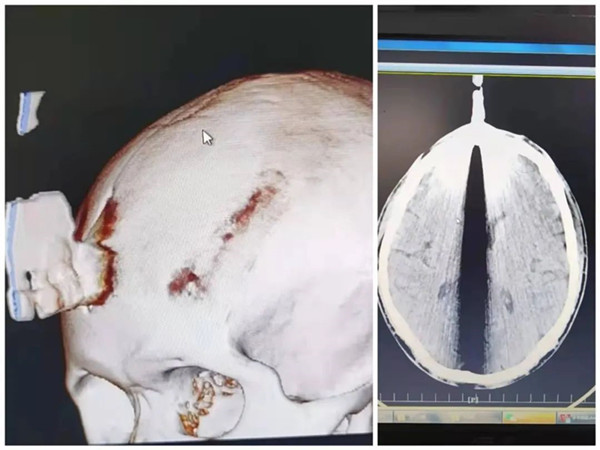

一小時后,救護車風(fēng)馳電掣開進縣人民醫(yī)院急診科。經(jīng)急診科醫(yī)生簡單檢查,確定患者為務(wù)工操作時鋸片破裂導(dǎo)致額部顱腦貫通傷并異物存留,創(chuàng)口活動性出血,病情危急,立即啟動綠色通道,患者轉(zhuǎn)入神經(jīng)外科病房。

“該患者顱腦貫通傷位置位于額部中線部位,該部位顱骨下有一重要的解剖血管即上矢狀竇,結(jié)合影像資料上矢狀竇損傷可能性極大,如輕易拔除異物及術(shù)中處理不當(dāng)將會出現(xiàn)大出血危及患者生命。”

本病例主刀者、副院長龍家柏稱,這次救治創(chuàng)造了又一個生命奇跡,綜合體現(xiàn)了錦屏縣人民醫(yī)院神經(jīng)外科急重癥創(chuàng)傷救治的水平。因鋸片穿通顱骨后刺通矢狀竇進入顱內(nèi),術(shù)中處理稍有不慎將會導(dǎo)致患者大失血,成功實施手術(shù)需要克服顱內(nèi)神經(jīng)二次損傷、顱內(nèi)大出血、術(shù)后感染等三大難關(guān),風(fēng)險極高。